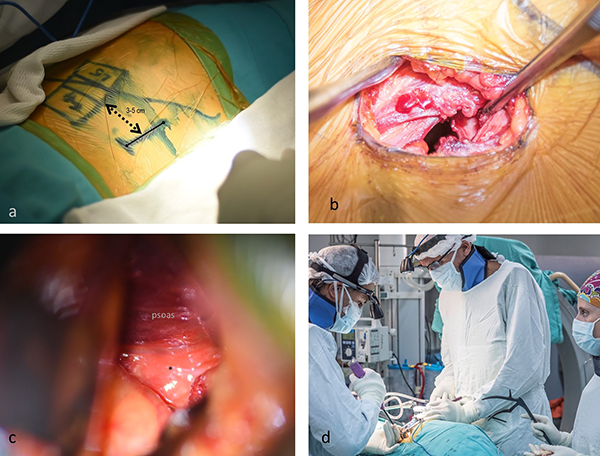

Se sugiere utilizar monitoreo neurofisiológico (electromiograma continuo, gatillado y estimulación radicular selectiva), debido a lo cual el método anestésico utilizado es anestesia total endovenosa. El paciente es posicionado en decúbito lateral derecho, con la mesa quirúrgica en posición neutra (Figura 3). Las piernas en extensión permiten tensar el músculo psoas, lo que genera su retracción y aumento del corredor de trabajo.7 Antes de comenzar se debe verificar con radioscopía una proyección lateral y anteroposterior estrictas, con platillos vertebrales paralelos en el nivel a tratar. Esto asegura que no haya alteraciones rotacionales que puedan llevar a mal posicionamiento de implantes o violaciones contralaterales. Se identifica el disco en la proyección lateral y luego se proyecta dicho espacio hacia la zona de la incisión en la región anterolateral del abdomen. El cirujano se coloca enfrente del abdomen del paciente, posicionando el equipo de radioscopía, el brazo del separador y el ayudante en el sector opuesto (a espaldas del paciente) (Figura 4d).

Figura 4: Imágenes intraoperatorias. a) Planificación de la incisión. Nótese la distancia desde la marcación radioscópica. b) La apertura de los músculos anchos del abdomen debe realizarse según la dirección de sus fibras, en forma roma. c) Reconocimiento de la grasa retroperitoneal (*). d) Situación del cirujano. Obsérvese que el mismo se posiciona del lado abdominal del paciente.

Incisión y disección de la pared abdominal

La incisión de 4-5 cm se realiza a 2 traveses de dedo (3,5 cm) por delante del espacio discal a tratar, en forma longitudinal, transversal u oblicua (Figura 4a). Debido a que la piel abdominal tiende a ser flexible y puede ser fácilmente retraída, pueden abordarse hasta 2 niveles con este tipo de incisión.2,7 Los músculos oblicuos y transverso son identificados y disecados en forma roma, siguiendo la dirección de las fibras musculares (Figura 4b). En esta etapa, los nervios que pueden encontrarse incluyen el subcostal, iliohipogástrico, ilioinguinal y cutáneo femoral lateral.8 En lo posible, deben ser respetados para evitar parestesias, disestesias y paresias postoperatorias. La fascia transversalis debe ser identificada y disecada lo más lateral posible para evitar el peritoneo. En este momento, la disección digital debe dirigirse hacia la cresta iliaca y hacia posterior, para evitar el ingreso al saco peritoneal. Cuando esta fascia se abre se tiene acceso a la grasa retroperitoneal.

Disección del espacio retroperitoneal e identificación del espacio discal

Luego de la apertura de la fascia transversalis, la bolsa peritoneal es identificada y, utilizando maniobras digitales suaves, desplazada hacia anterior (Figura 4c). Mediante palpación se identifica el músculo psoas en profundidad, el músculo cuadrado lumbar hacia posterior, el polo inferior del riñón izquierdo hacia cefálico. Mientras más amplia es esta disección hacia cefálico y caudal, menos chances hay de lesionar el uréter o las vísceras. El uréter y la vena gonadal suelen encontrarse en la misma vaina de la cara anterior del psoas, y deben ser desplazados hacia anterior del paciente, junto con el peritoneo. El borde anterior del músculo psoas es identificado, y, en relación al mismo, el corredor de trabajo y el disco intervertebral. En este punto, cualquier adherencia entre el peritoneo y el psoas debe ser suavemente liberada mediante maniobras romas. El borde lateral del ligamento longitudinal anterior puede ser identificado, como elemento indicador del extremo medial del sitio de trabajo.7